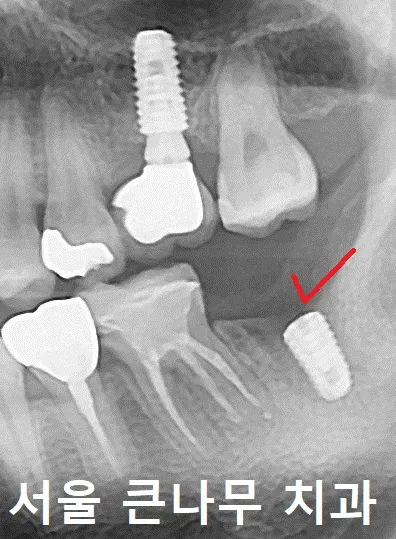

임플란트 식립 후 내려온 치아를 당겨주기 위한 나사(mini-implant)를 잇몸뼈에 안팎으로 심어 주었습니다.

잇몸뼈 안쪽(왼), 잇몸뼈 바깥쪽(오)

미니임플란트와 치아에 버튼을 달아 연결해 주었습니다.